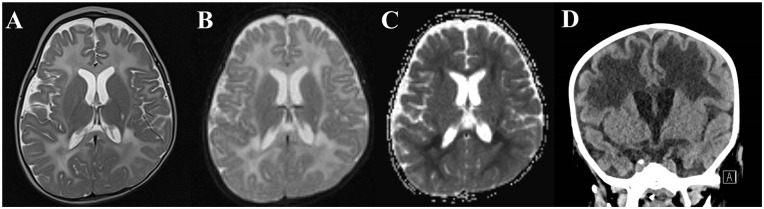

Glutaredoxin 5 (GLRX5) is a mitochondrial protein encoded by the GLRX5 gene, which is essential for cellular redox homoeostasis, lipoic acid synthesis, and iron-sulfur cluster transfer. Rare cases of pathogenic GLRX5 mutations have been associated with sideroblastic anemia and non-ketotic hyperglycinemia with progressive spasticity and cavitating leukoencephalopathy. We report an 11-month-old child, who died following aspiration, with severe cardiomyocyte mitochondrial abnormalities and cerebral white matter degeneration in the context of a homozygous GLRX5 variant (c.208A>G, p.S70G).